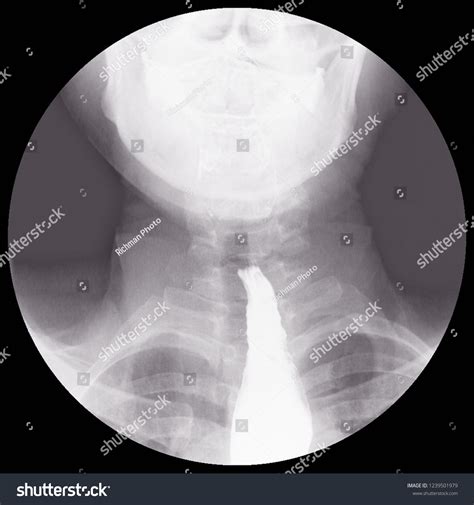

When a patient presents with dysphagia (difficulty swallowing), the Achalasia Barium Swallow serves as a cornerstone diagnostic test. During this procedure, the patient drinks a liquid containing barium, a contrast material that coats the inner lining of the esophagus. As the patient swallows, a radiologist uses fluoroscopy—a continuous X-ray beam—to observe the movement of the liquid down the esophagus in real-time.

The hallmark finding on a barium swallow study for achalasia is the "bird’s beak" appearance. This occurs because the LES remains tightly closed, causing the esophagus above it to dilate and taper to a narrow point, resembling the beak of a bird. This visual evidence is often the first major indicator that confirms a diagnosis of achalasia.